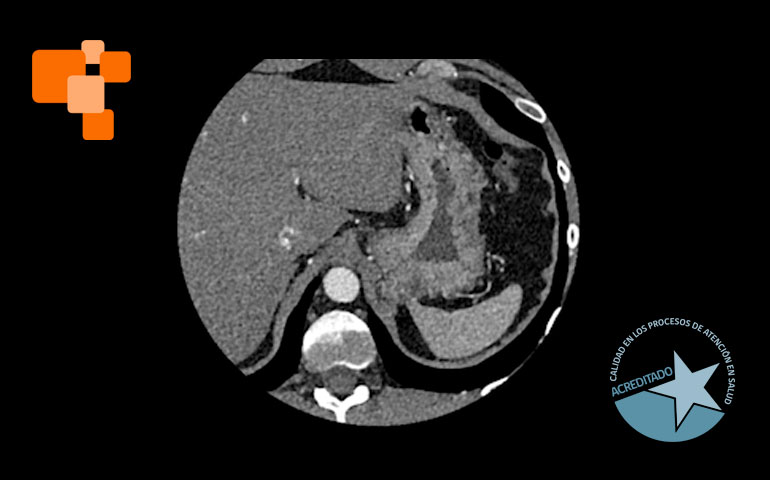

El TAC de calcio coronario es un examen de alta complejidad, realizado usualmente en centros de imagenología avanzada, mide el calcio en las arterias coronarias para evaluar el riesgo de eventos cardíacos futuros. Al proporcionar un score de calcio coronario, permite a los médicos identificar la acumulación de calcio y ajustar tratamientos para prevenir la aterosclerosis, una causa principal de ataques cardíacos. Según expertos, médicos especialistas en cardiologías lo sugieren principalmente para aquellos en riesgo moderado, pacientes que no han tenido síntomas, pero poseen factores de riesgo como hipertensión o colesterol alto.

La tomografía computada para el cálculo del score de calcio coronario permite identificar y cuantificar calcificaciones antes de que se manifiesten síntomas de enfermedad cardíaca, facilitando intervenciones tempranas. Es una técnica de diagnóstico por imagen que, a diferencia de otros métodos más invasivos, ofrece una evaluación rápida y no invasiva de las coronarias.